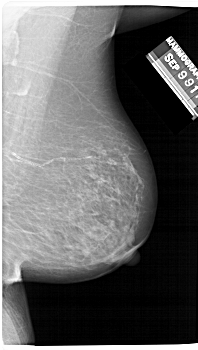

A_1481_1.RIGHT_CC

RIGHT_CC LINES 6046 PIXELS_PER_LINE 3046 BITS_PER_PIXEL 12 RESOLUTION 43.5 NON_OVERLAY